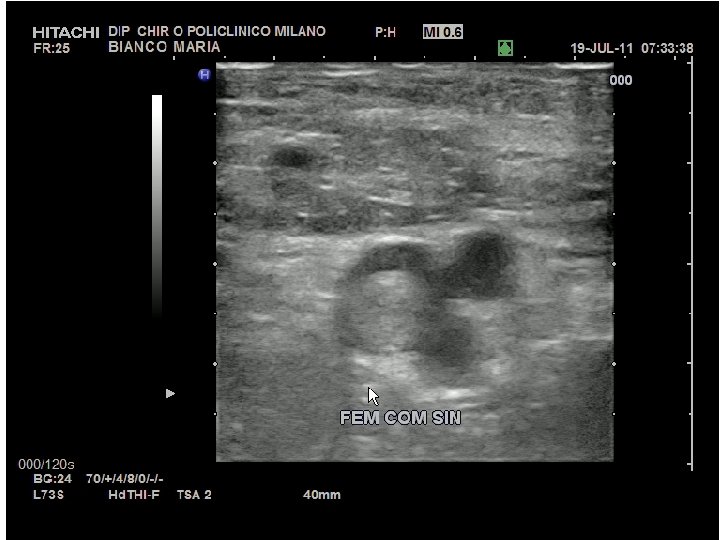

LA COMPRESSIONE ULTRASONORA COME SI ESEGUE ? - IN SCANSIONE TRASVERSALE - AUMENTANDO LA PRESSIONE DELLA SONDA - INTERESSA IL COLLABIMENTO DELLE PARETI - CONFRONTO CON L’A. CONTROLATERALE

LA COMPRESSIONE ULTRASONORA DOVE SI ESEGUE ? SOLO IN 2 SEDI : - V. FEMORALE COMUNE (CRANIALMENTE ALLA ORIGINE DELLA SAFENA) - V. POPLITEA (CRANIALMENTE ALLA ORIGINE DELLE V. GEMELLARI) - … E BASTA !

CUS DA SOLA ? SOLO IN DUE PUNTI ? FACILE DA APPRENDERE ED AFFIDABILE ? DUE IMMAGINI PER UN ESAME SENZA AMBIGUITA’

(BASE)

( DOPO CUS) … MA NON E’ SEMPRE COSI’ !

L’IMMAGINE DA ALLEGARE AL REFERTO